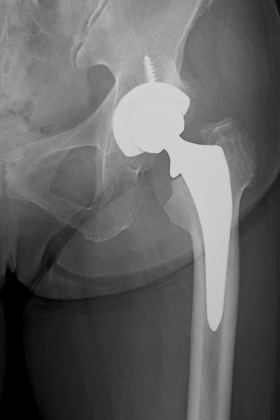

人工股関節置換術とは、傷んで変形した関節を人工の関節に置き換える手術です。人工関節の表面は滑らかで神経もないため、この手術を受けることによって、関節は滑らかに動くようになり、痛みもほとんど感じなくなります。痛みなく歩けるようになると、日常生活を送りやすくなり、生活の質(QOL)を改善することができます。

手術では、まず変形した大腿骨頭を根元から切除し、傷んだ寛骨臼の表面の骨を削って取り除きます。寛骨臼側には金属のカップを骨に固定し、そのカップの内側に超高分子量ポリエチレン製の人工の軟骨(ライナー)をはめ込みます。大腿骨側には杭状の金属(ステム)を骨の中に挿入し、その先にセラミック製の人工の骨頭(ヘッド)を設置します。人工股関節はライナーとヘッドの間で滑らかに動く構造になっています。

人工股関節を骨に固定する方法には、「骨セメントを使用しない方法(セメントレス固定)」と「骨セメントを使用する方法(セメント固定)」の2種類があります。当院では、患者さんの年齢、骨の質、変形の程度などによって最適な方法を選択しています。

![]() 術後レントゲン |